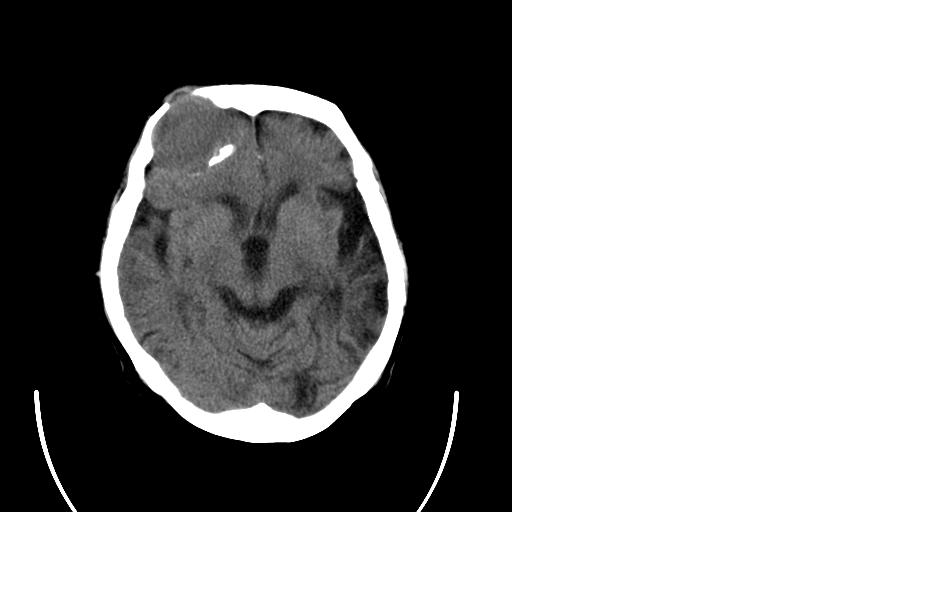

女,77岁,渐进性突眼2年,无其他明显症状

病变位于起源于右侧筛窦,右侧眼球受压移位,右侧大脑半球额叶白质受压塌陷,水肿不明显.额骨呈压迫性骨质吸收变薄.考虑脑膜瘤,建议增强吧

右额窦粘液囊肿,向前累及筛窦并进入眼眶使眼球前突;向下进入颅内右额叶脑质及侧脑室受压

病变应起源于右侧额窦/或额骨板障,肿块周围骨包壳尚完整,呈膨胀挤压改变,右侧眼球受压移位,右侧大脑半球额叶白质受压塌陷,水肿不明显.考虑为良性病变,骨纤维瘤/或骨嗜酸性肉芽肿? 建议增强吧

支持:病变的起源我乐意定在右额窦。右额窦粘液囊肿或粘液腺癌累及筛窦、眼眶使眼球前突;向下进入颅内右额叶脑质及侧脑室受压变形。

右侧筛窦类圆形实质性肿块向颅内呈膨胀性生长,边缘较为光滑,其内似见囊性低密度影,边缘骨壁受压变薄移位,部分骨质缺损破坏

定位:来源右额窦。定性:良性占位—额窦黏液囊肿。理由1、病灶中心位于右额窦区,侵及筛窦并向下向前压迫眼球2、骨质呈膨胀性改变,骨质弓形变薄但骨壳完整,如为恶性骨质应为侵蚀性破坏3、黏液囊肿好发于筛窦、额窦。